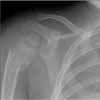

The skull, the long bones of the extremities, and the clavicle are most susceptible to injury following a seemingly insignificant accidental fall.5,6 However, these are the same bones, along with the ribs, that are fractured when a child is intentionally injured. Although serious sequelae, such as depressed skull fractures, can result from a low fall, the vast majority of children do not sustain major injury.5-8

As with skull fractures, rib fractures are of extreme concern. The distal or mid clavicle can be easily injured in an accidental fall, but a fracture of the most medial aspect of the clavicle is particularly worrisome.22 The long bones are commonly injured in an accident, but in a child older than 1 year, the long bones (femur, humerus, tibia, and forearm bones) are also the most common location of non-accidental injury.22

Imaging studies are often necessary in the assessment of an infant or young child with an obvious or suspected injury. The skeletal survey (Table 3) is recommended and is mandatory in all cases of suspected abuse in children younger than 2 years.24 However, it has little value in children older than 5 years.25 Patients between ages 2 and 5 years are assessed on an individual basis.

If clinical findings point to a specific injury site, that anatomic region should be evaluated with a radiograph--regardless of the child's age.25 An experienced radiologist should be present while imaging is performed to ensure that high-resolution images of good quality are obtained. If the initial skeletal survey is unremarkable but abuse is still strongly suspected, a repeated skeletal survey in 2 weeks may offer greater yield in discovering occult fractures.26 A bone scan is another option for searching for occult fractures: the need for this modality is determined on a case-by-case basis.